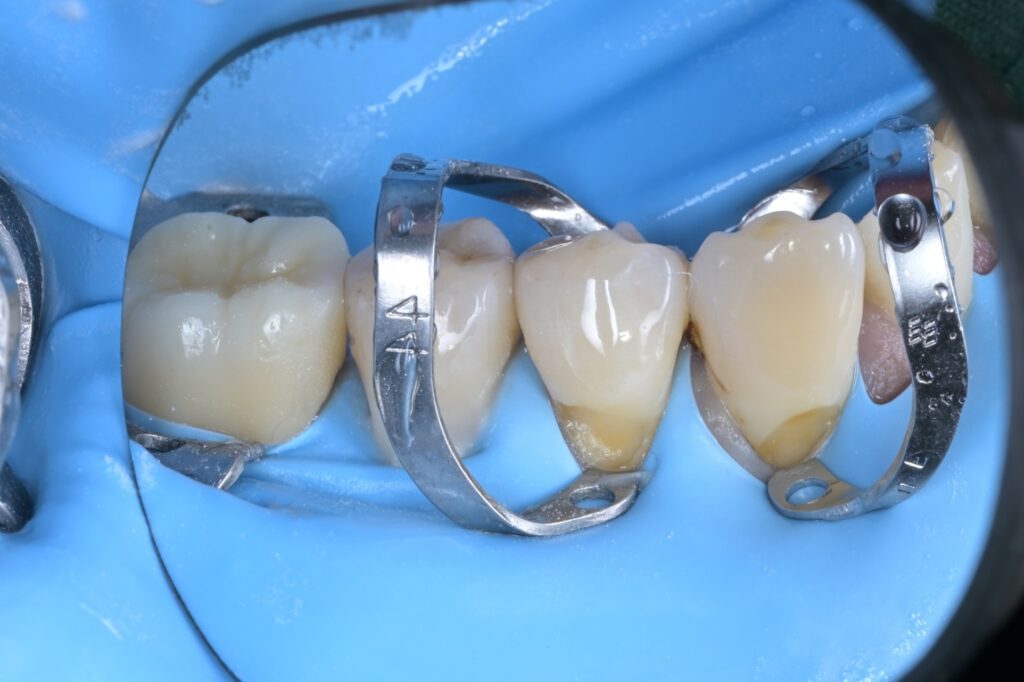

STEP 4 ~ 5. 앞쪽 치아 격리 (클램프 장착)

이제 앞쪽에 있는 제1소구치(4번)와 송곳니(3번)를 치료할 차례입니다. 이 부위는 잇몸 라인이 더 깊기 때문에, 잇몸을 살짝 아래로 내려주는 특수 클램프(금속 고리)를 각각의 치아에 걸어줍니다.

"원장님, 이렇게까지 해야 하나요?"

네, 해야 합니다. 저 금속 고리가 잇몸을 살짝 밀어줘야 치료할 부위가 확실히 보이고, 접착제가 잇몸에 닿지 않아 치료 성공률이 높아집니다.